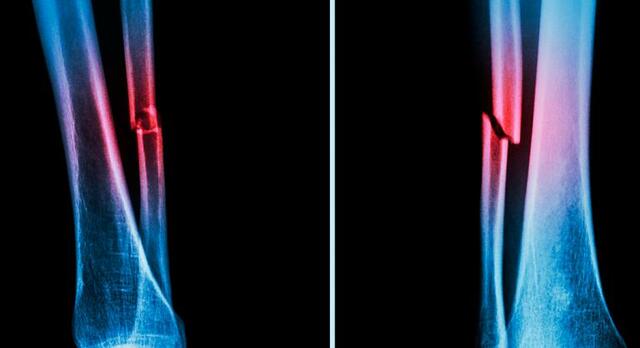

A las pocas semanas de que Roentgen descubriera los rayos X, se hizo evidente las posibilidades de esta técnica para el diagnóstico de las fracturas, pero los efectos nocivos agudos, hicieron que el personal de los hospitales se percatara de la necesidad de evitar la sobrexposición. Tiempo después vieron efectos graves y nocivos similares. No se hizo una coordinación adecuada para proteger al personal expuesto a los rayos X y a las radiaciones gamma provenientes del radio.

El 8 de noviembre de 1895, Wilhelm Róntgen, al hacer pasar una corriente eléctrica de alto voltaje a través de un tubo vacío, observó fortuitamente, en unos cristales de sal de bario próximos, que éstos resplandecían con brillo fluorescente. Colocó su mano entre el tubo y las sales, y vio que aquélla, con la silueta de los huesos de sus dedos, proyectaba su sombra sobre las sales.

3 de Febrero de 1896, Se realiza el primer examen médico por rayos X en EEUU, a cargo de los hermanos Frost, sobre la mano de un joven con molestia en la mano.

Los primeros procedimientos radiológicos, necesitaban largos tiempos de exposición, por lo que las lesiones por radiación fueron bastante frecuentes.